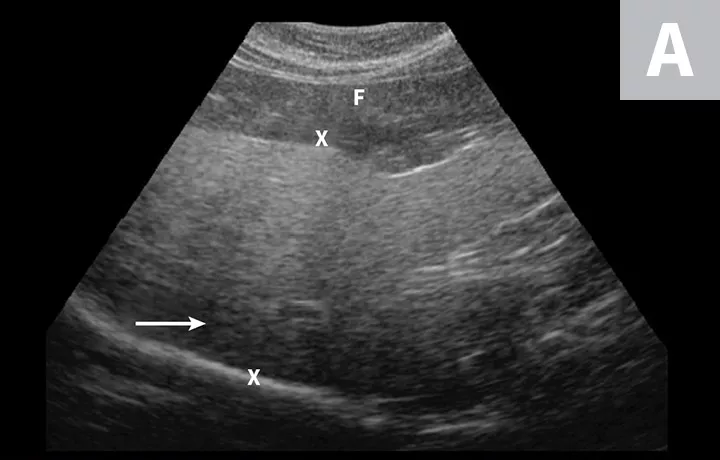

Imaging of a 1-year-old neutered male standard poodle presented with anorexia, lethargy, vomiting, hypoalbuminemia, hypoproteinemia, and cranial abdominal organomegaly. Transverse (A) and sagittal (B) ultrasound of the liver and gallbladder (GB). The liver is enlarged (with increased distance off the stomach from the diaphragm, rounded borders, and extension ventral to the stomach), diffusely hyperechoic, and homogenous. The gallbladder is moderately distended with a normal wall and content. Radiographs demonstrate hepatomegaly and splenomegaly (C). Abdominal ultrasound images revealed splenic enlargement with a mildly mottled architecture and a solitary hypoechoic nodule (D; arrowheads). The pancreas is enlarged and lobulated with multiple hypoechoic tracts and a peripheral capsule (E; between electronic cursors [X’s]). The jejunal lymph nodes are severely enlarged (F; between electronic cursors [X’s]), more than expected for a young dog. The combination of severe hepatosplenomegaly and lymphadenomegaly make systemic disease (eg, infectious, neoplastic) most likely. The appearance of the pancreas is due to pancreatic edema secondary to hypoproteinemia. Acute liver injury was diagnosed, and lymphoma was diagnosed based on hepatic and splenic cytology.